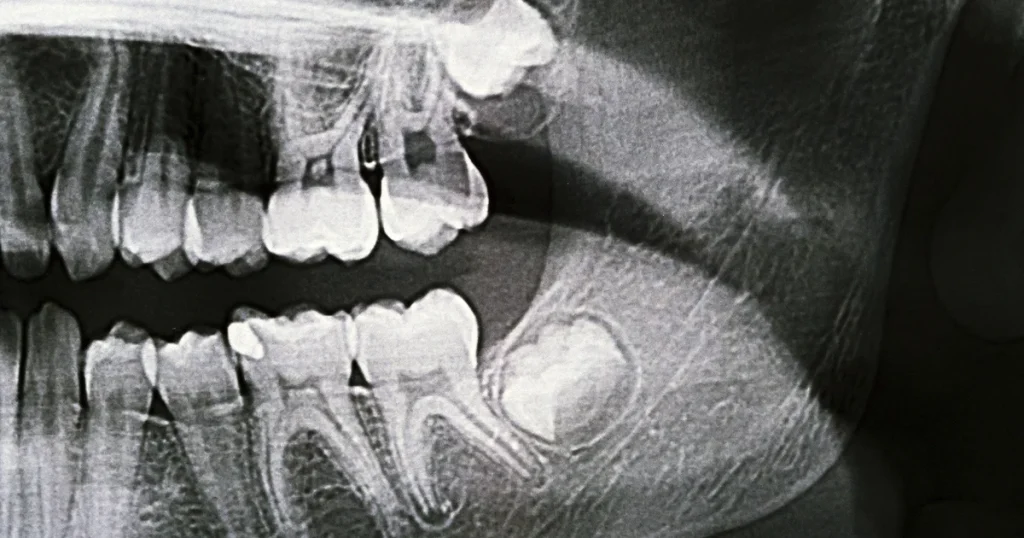

Alt du behøver at vide om visdomstænder